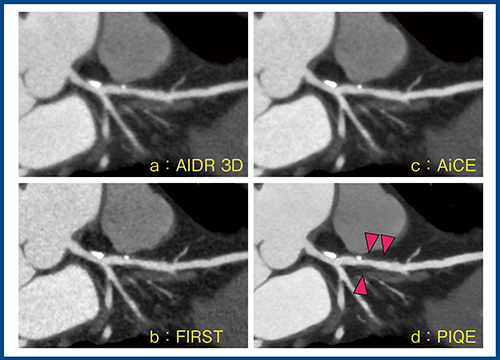

図5の症例は,左前下行枝(LAD)近位部に偏心性のプラークを認める。PIQE(d)では,ほかの再構成法と比較して血管の鮮鋭度が増しており,プラークの存在をよりはっきりと確認できる(▲)。

図5 冠動脈プラークの描出